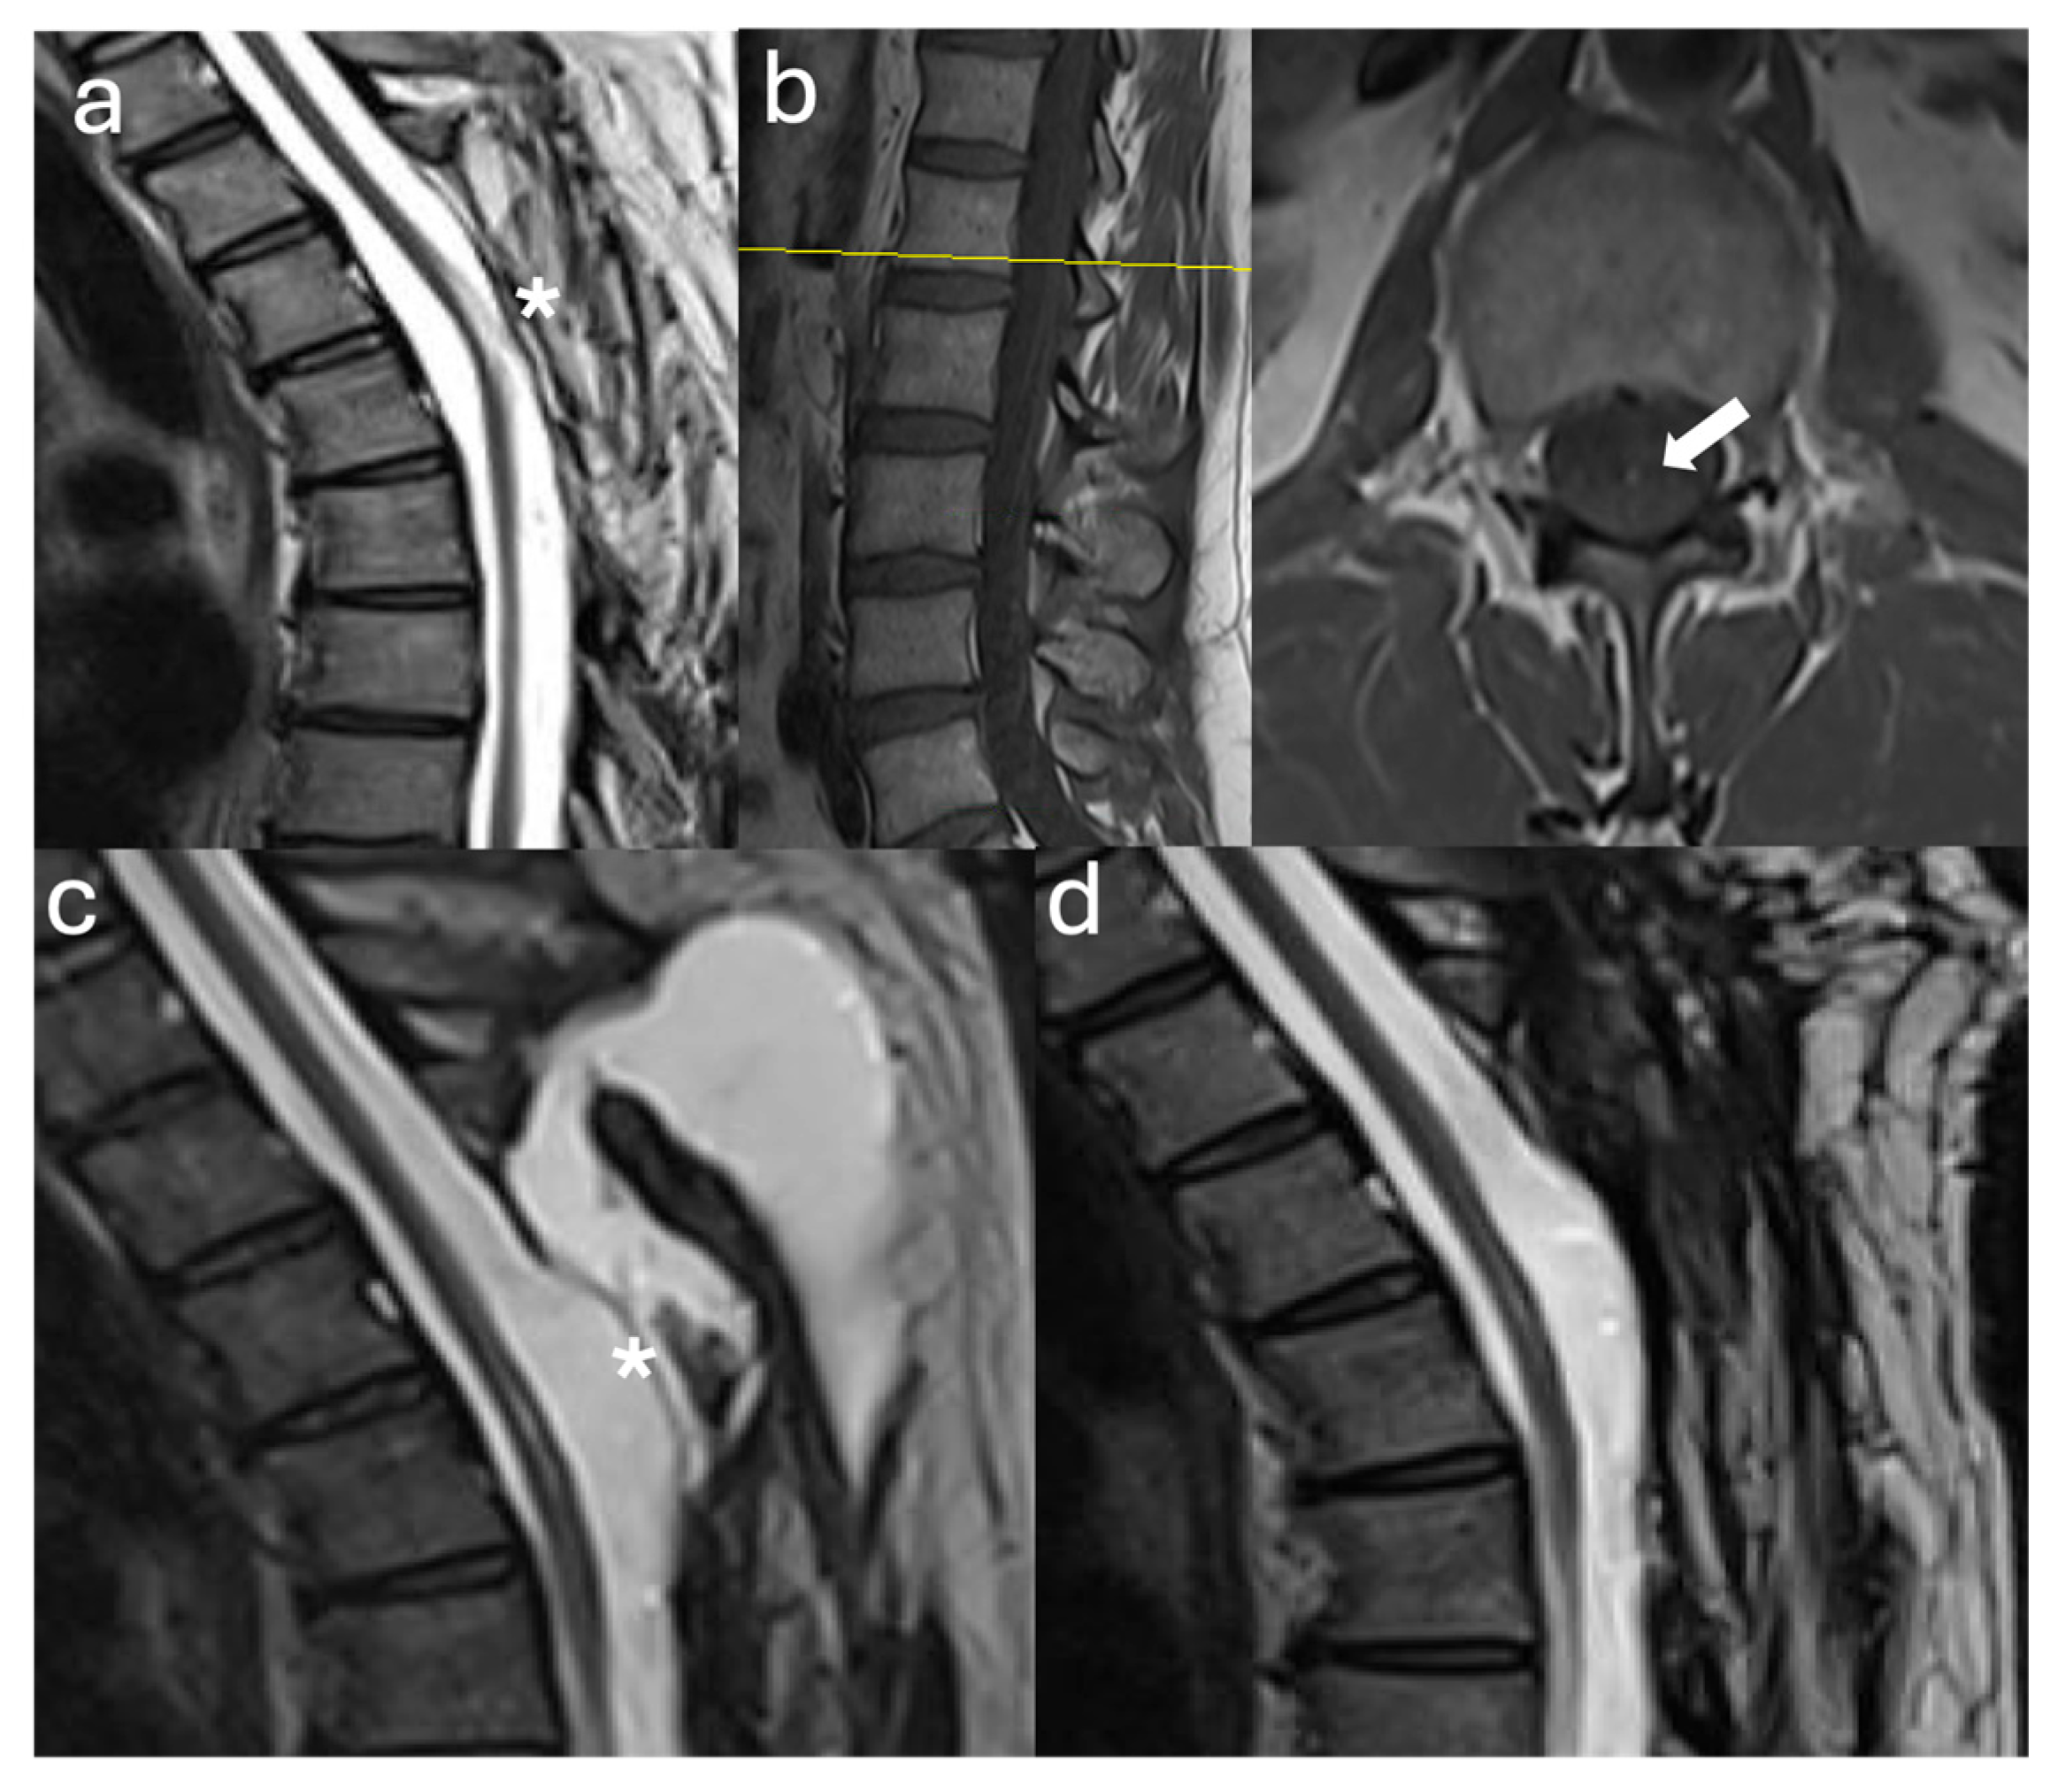

3.2.1. Case #1

3.2.2. Case #2

3.2.3. Case #3

3.2.4. Case #4

3.2.5. Case #5